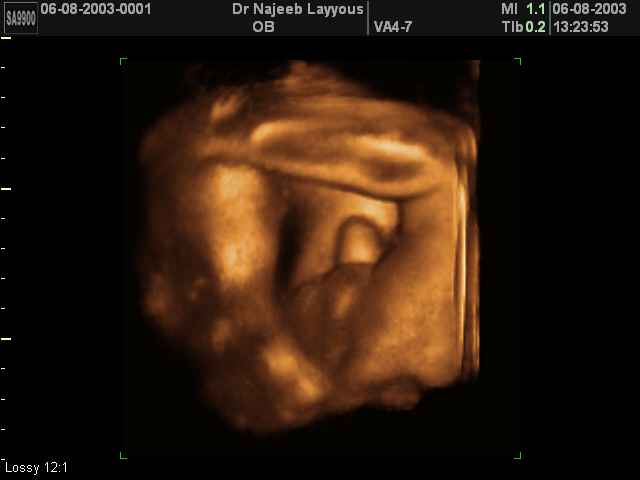

- Fetal Parts Ultrasound Scan Photos